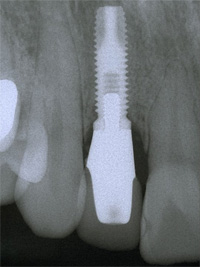

| 失った部分にインプラントを1本埋入します。従来は健全な両隣の歯を削ってブリッジを用いて治療していましたが、インプラントを用いると健全な歯を削ることなく治療を行うことが出来ます。 |

| インプラントの上のクラウンにより、あなたの咀嚼機能と自然な風貌が回復するでしょう。 |